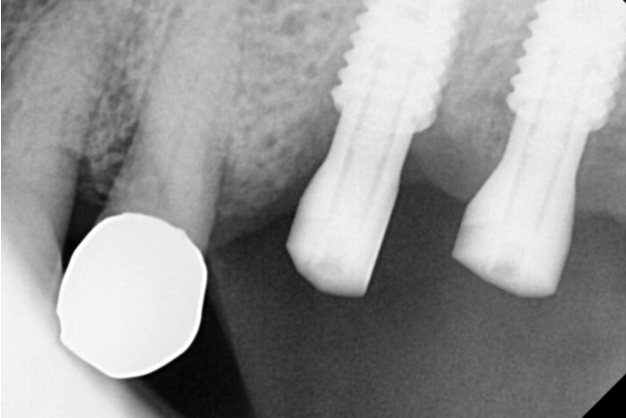

231030

강일역 임플란트 치료 후 사진입니다.

치아 크라운 빠짐 부분과

잇몸이 내려갔던 치아

문제의 2개 치아를 발치 후

임플란트 완료하였습니다.